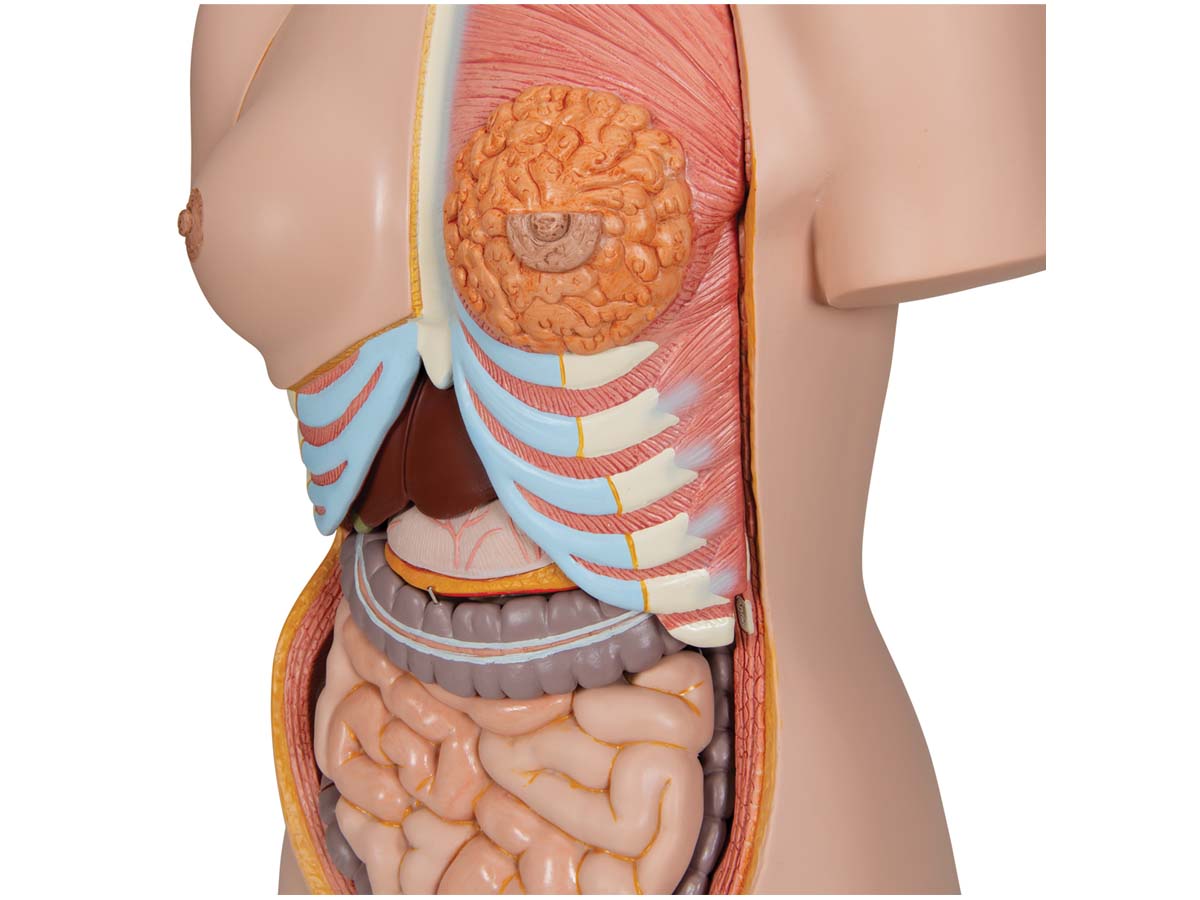

Luxus Torso Modell, mit weiblichen & männlichen Geschlechtsorganen, 24-teilig

Luxus Torso Modell, mit weiblichen & männlichen Geschlechtsorganen, 24-teilig – 3B Smart Anatomy

Der 3B Scientific Luxus-Torso bietet Ihnen alle Möglichkeiten für ausführliche Demonstrationen. Sie erhalten hunterprozentige Qualität und einen hohen Grad an Detailarbeit. Die Beschaffenheit der erweiterten Torso-Version ist beeindruckend, genau wie sein Preis! Beantworten Sie mit seiner Hilfe alle Fragen zur inneren Anatomie des Menschen. Er ist zerlegbar in:

– 3-teiligem Kopf

– 2-teiligem Magen

– 4-teiligem Darmpaket

– Weibliche Brustdecke (2-teilig)

– 2 Lungenhälften

– 2-teiliges Herz

– Leber mit Gallenblase

– Vordere Nierenhälfte

Alle Organe in diesem menschlichen Torso sind von Hand bemalt.